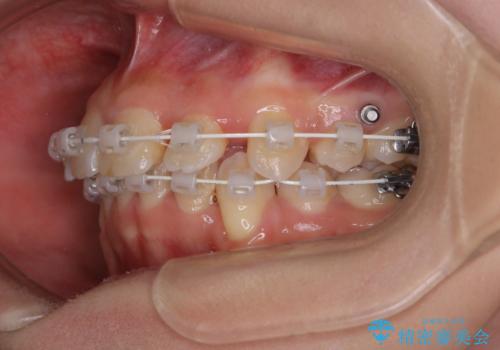

- 矯正装置

- 審美装置(ワイヤー)

- 治療期間

- 1年10ヶ月

- 治療回数

- 30回以上

- 出っ歯が気になるとご相談にいらした方です。抜歯して歯を並べました。深かった噛み合わせも改善させることが出来ました。

噛み合わせが元々深い方は一般的に噛む力が強く、治療に時間がかかる傾向にあります。治療前の想定よりも短期間でスムーズに治療を終える事ができ、大変喜んでいただけました。リテーナーによる保定もしっかり行っていただいており、後戻りなく快適にすごして頂けているとのことです。